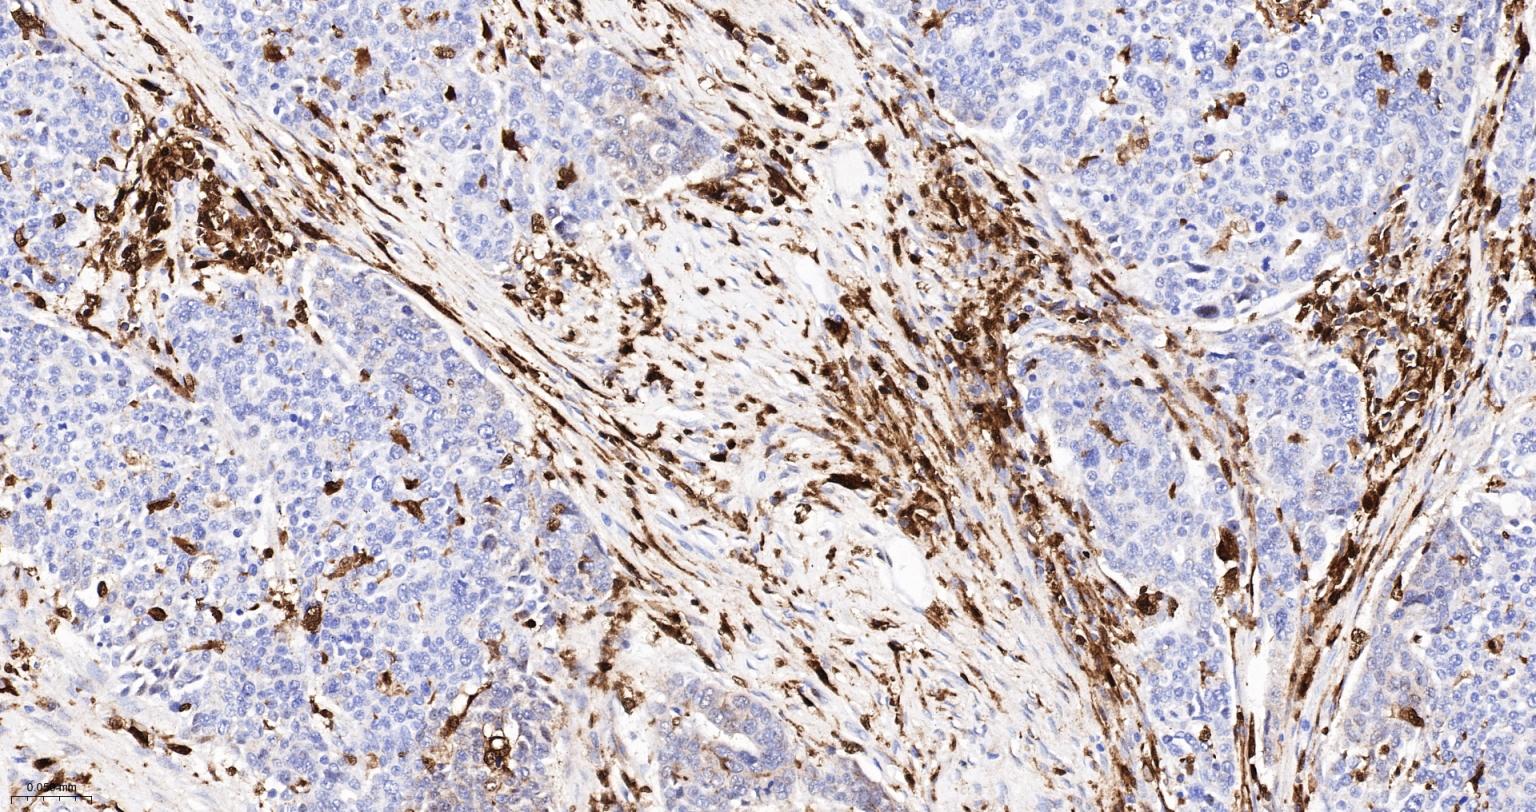

| 英文名称 | CD16 Recombinant Rabbit mAb |

| 中文名称 | FC段γ受体3/免疫球蛋白G Fc段受体III重组兔单抗 |

| 产品应用 | ICC/IF=1:100-500, Flow-Cyt=1:100-200, IHC-P=1:200-2000, IHC-F=1:200-2000, IF=1:200-2000 Not yet tested in other applications. |

| 交叉反应 | Human, Rat |

| 组织特异性 | Expressed on natural killer cells, macrophages, subpopulation of T-cells, immature thymocytes and placental trophoblasts. |

| 背景资料 | This gene encodes a receptor for the Fc portion of immunoglobulin G, and it is involved in the removal of antigen-antibody complexes from the circulation, as well as other responses, including antibody dependent cellular mediated cytotoxicity and antibody dependent enhancement of virus infections. This gene (FCGR3A) is highly similar to another nearby gene (FCGR3B) located on chromosome 1. The receptor encoded by this gene is expressed on natural killer (NK) cells as an integral membrane glycoprotein anchored through a transmembrane peptide, whereas FCGR3B is expressed on polymorphonuclear neutrophils (PMN) where the receptor is anchored through a phosphatidylinositol (PI) linkage. Mutations in this gene are associated with immunodeficiency 20, and have been linked to susceptibility to recurrent viral infections, susceptibility to systemic lupus erythematosus, and alloimmune neonatal neutropenia. Alternatively spliced transcript variants encoding different isoforms have been found for this gene. [provided by RefSeq, Aug 2020] |